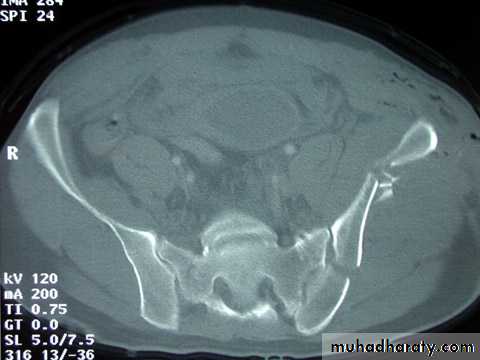

CT SCAN :

CT is the modality of choice for accurately showing acetabular or pelvic ring fracturesOther investigations :